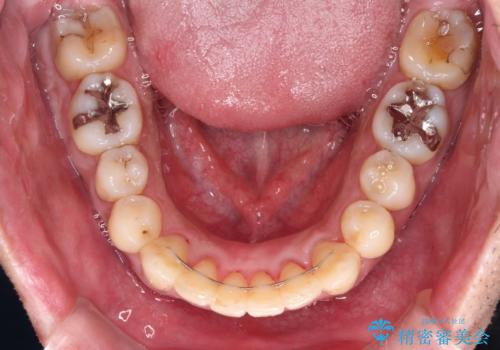

下顎骨が顕著に右側にずれている インビザラインによる咬合改善

- 上下前歯のデコボコを気にして来院された患者様です。

下顎骨が顕著な左右差を持って成長したため、右側にずれている状態でした。

デコボコは抜歯をすることなく解消できる程度であったため、インビザラインにより矯正治療を行うこととしました。